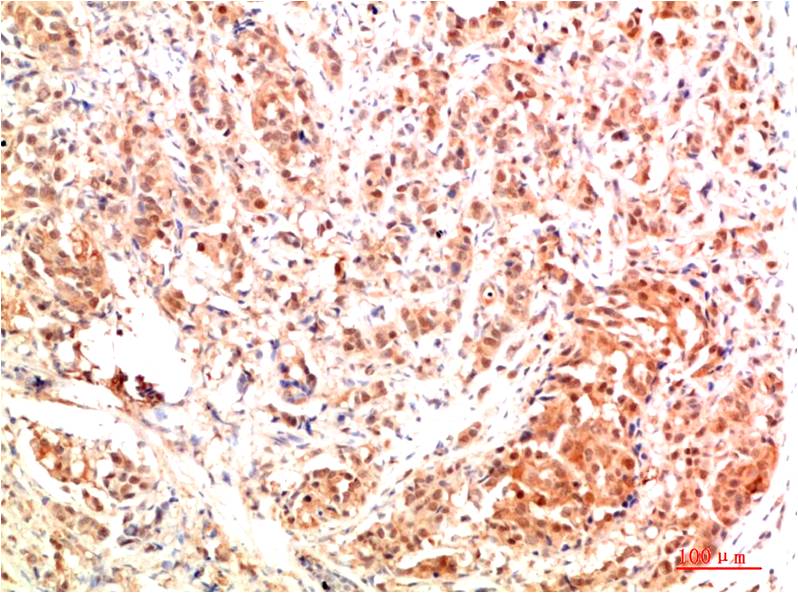

Acetyl P53(K382) Mouse Monoclonal Antibody(5H10)

Applications :IHC

| Recommended dilutions: | IHC: 1:100-200 |

| Specificity: | The Acetyl P53(K382) Mouse Monoclonal Antibody can detects endogenous Acetyl P53(K382) proteins. |